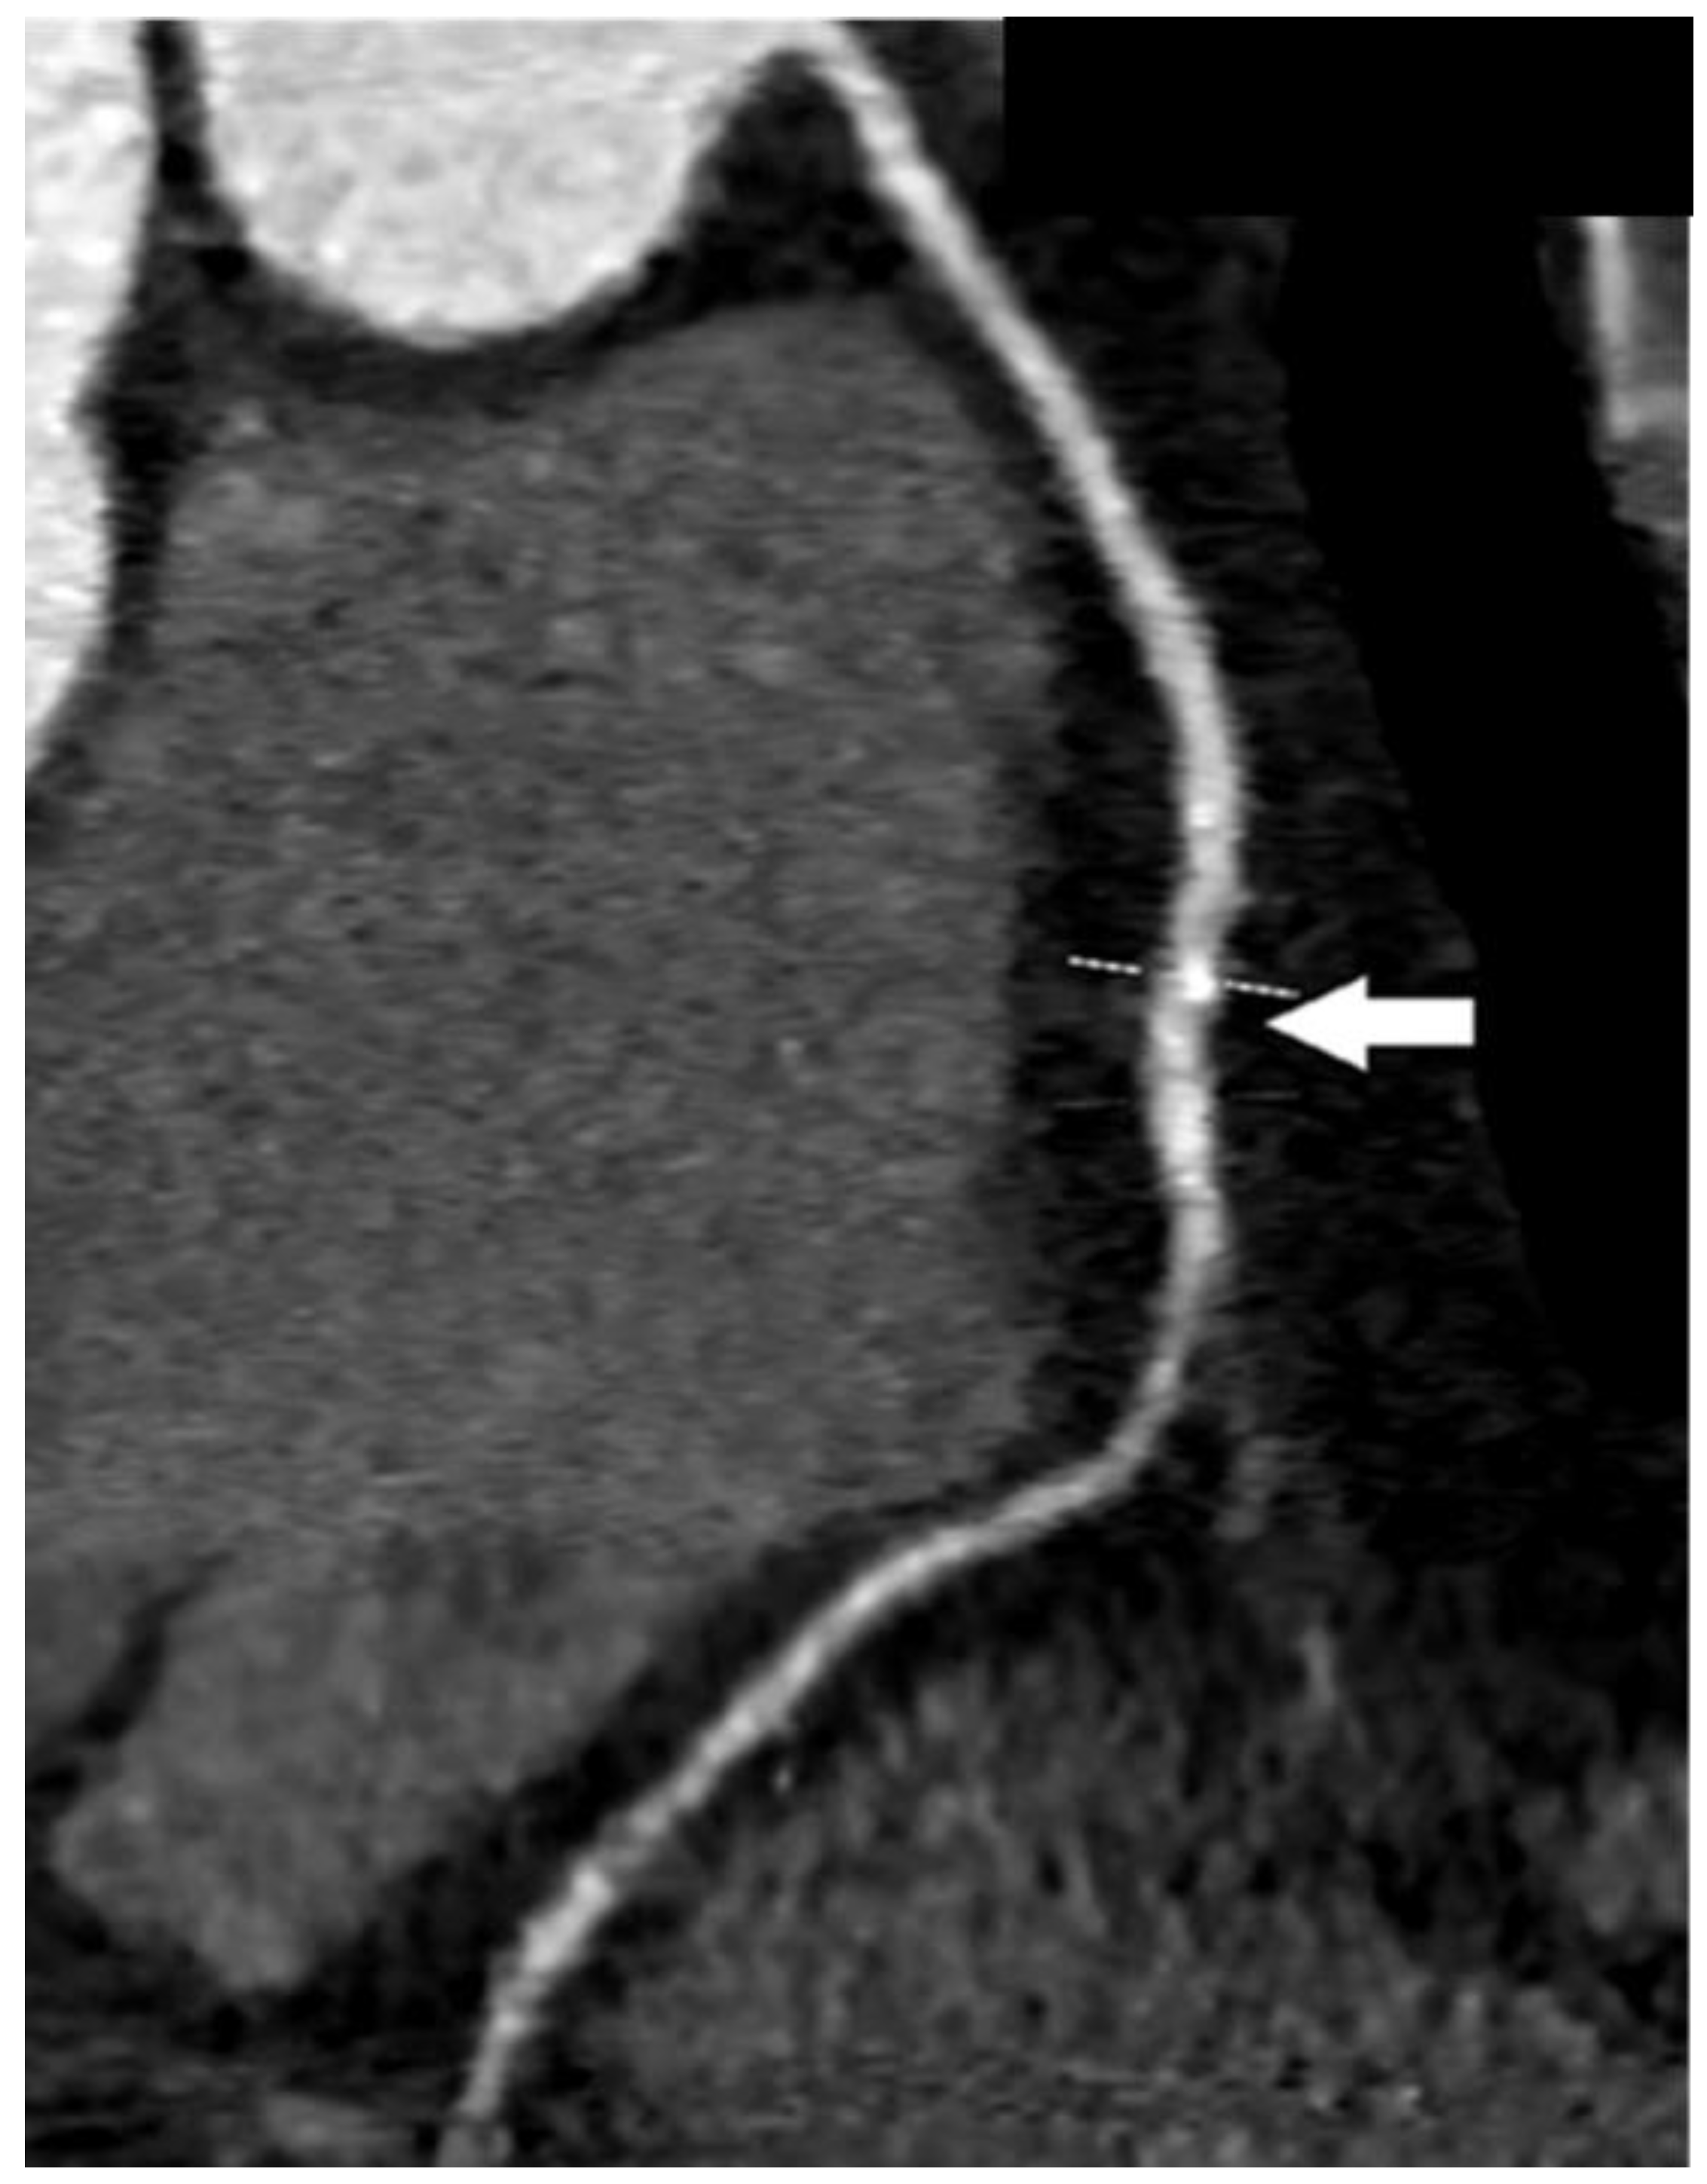

| Coronary computed tomographic angiography (CCTA) | Assess the dimensions and configuration of the arterial wall and lumen Plaque characterization Evaluating the presence, location, and characteristics of aneurysm and stenotic regions Reconstruction of intricate anatomical structures in a three-dimensional model | Noninvasive Greater specificity in cases of aneurysms and thrombosis Suitable for follow-up | Expensive Involves ionizing radiation Requires intravenous contrast media Dependent on an imaging specialist |